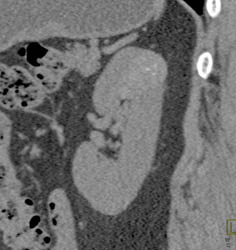

High Density Renal Cyst